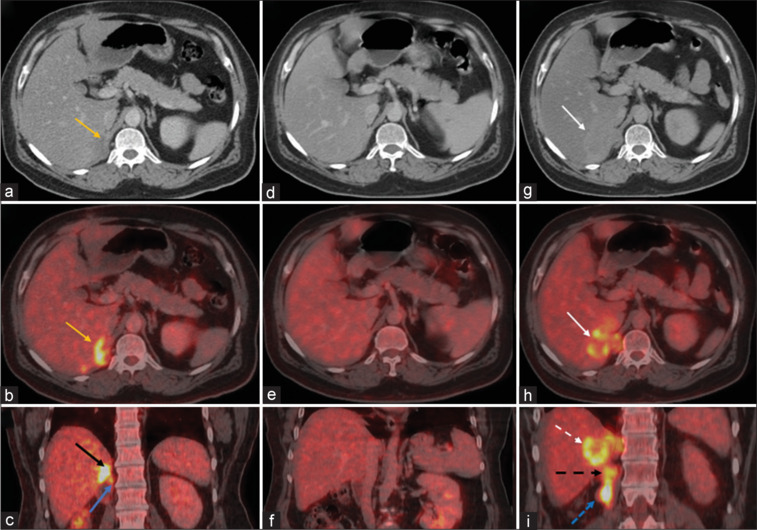

Metastatic renal osteosarcoma is a rare entity. We report a case of a 52-year-old male postright nephrectomy status presented to us with metastatic renal osteosarcoma. 18-fluorine- fluorodeoxyglucose (18F-FDG) avid lesions were seen in the right renal bed with extension to adjacent hepatic parenchyma. The patient exhibited a favorable response to 6 cycles of carboplatin and doxorubicin with no FDG avid lesions in the postchemotherapy follow-up scan. On 6-month follow-up scan, scan findings reveal a recurrent lesion at the renal bed region infiltrating psoas muscle and liver metastatic lesion. This case highlights the use of 18F-FDG positron emission tomography/computed tomography in metastatic recurrent extraskeletal osteosarcoma.

转移性肾骨肉瘤是一种罕见的肿瘤。我们报告一个52岁男性直肾切除术后转移性肾骨肉瘤的病例。18-氟-氟脱氧葡萄糖(18F-FDG)病变可见于右肾床,并扩展到邻近的肝实质。在化疗后随访扫描中,患者对卡铂和阿霉素6个周期的治疗反应良好,无FDG明显病变。在6个月的随访扫描中,扫描结果显示肾床区复发病变浸润腰肌和肝转移灶。本病例强调了18F-FDG正电子发射断层扫描/计算机断层扫描在转移性复发骨外骨肉瘤中的应用。